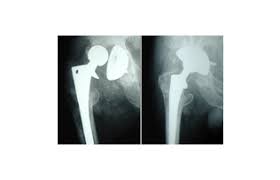

- 고관절 전치환술(Total Hip Arthroplasty, THA): 골관절염이나 류마티스 관절염, 골절 등에 널리 사용되는 방식으로, 관절 전체를 인공 관절로 교체합니다.

- 정기 검진: 엑스레이 또는 CT로 인공관절의 상태 확인